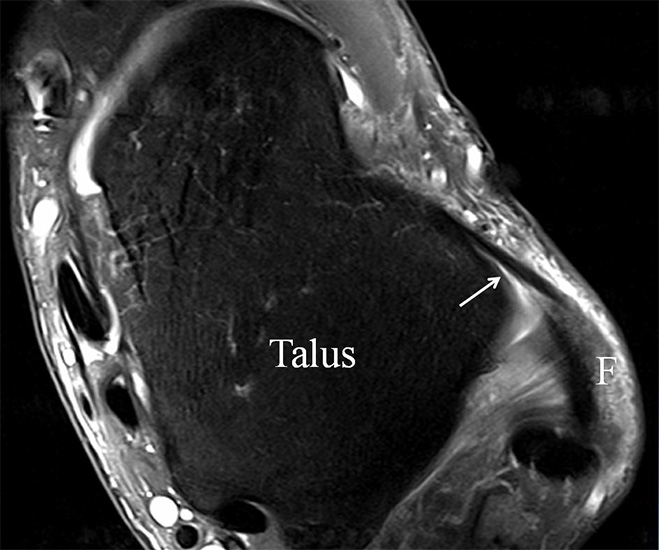

PD fs HR axial. Klare Darstellung eines filigranen, knapp über 1 mm breiten LFTA (Pfeil). Fibula (F).

Abbildung 3

Das LFTA verbindet die antero-inferiore Fibulaspitze mit dem Processus lateralis tali und inseriert hier an einem oder zwei kleinen Tuberkeln 3. Der in Neutralposition horizontale Verlauf erleichtert die kernspintomographische Darstellung in dieser Standardebene. Das LFTA weist durchschnittlich eine Breite von knapp über 2 mm auf 4. Somit sind bei einer Routinedarstellung in 3 mm Schichtdicke Anschnittsphänomene, die die Diagnostik erschweren, regelmäßig anzutreffen. Dementsprechend sind auch die ligamentären Subfaszikel nicht zu differenzieren. In koronarer Darstellung ist dies aufgrund der hohen Auflösung in der Schichtebene jedoch möglich (Abb. 2 a-c), wobei hier wiederum eine Integritätsbeurteilung des Bandes erschwert ist. Unter Verwendung hochauflösender Techniken im Millimeterbereich (Schichtdicke) sind hingegen auch in der axialen Ebene die subfaszikulären Strukturen zu beurteilen (Abb. 3).